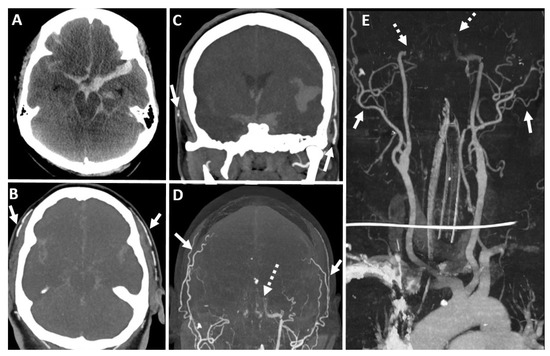

7.4. Computed Tomography (CT) Brain

7.5. Computed Tomography Angiography (CTA) Brain

7.6. Computed Tomography Perfusion (CTP) Brain